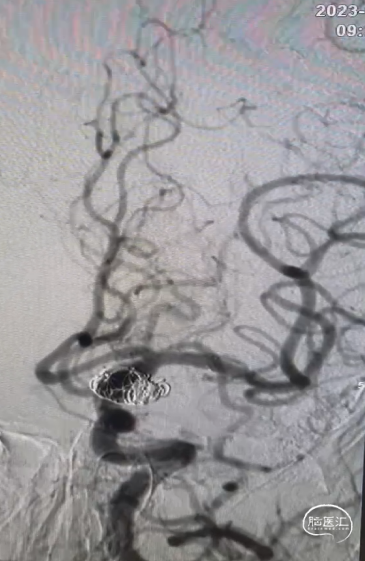

术后造影显示各分支血管通畅,动脉瘤不再显影。

术后影像及随访

患者术后恢复良好,术后4天出院,出院mRS 0分。

术后3个月门诊随访,复查头颈部CTA:动脉瘤不显影,载瘤动脉通畅。

复查CTP未见明显异常。